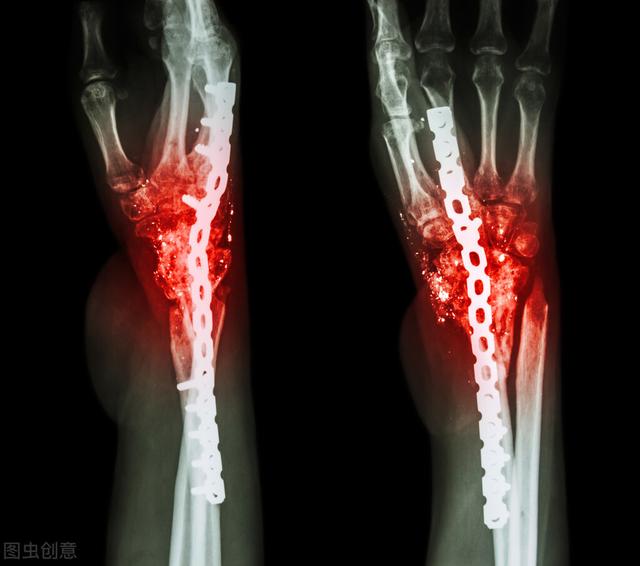

骨折后伤口溃烂不愈合怎么办?

骨折后伤口溃烂不愈合的主要原因是:开放性损伤术后伤口感染、患者长期营养状况不良、排异反应、骨髓炎等 。

3、排异反应 , 主要是患者对于伤口缝线及内植物有排异反应 , 导致创面迟迟不能愈合出现溃烂 , 对于这种情况做好创面换药及清理 , 同时去除内部固定 , 待创面新鲜、细菌培养阴性、炎症指标都正常 , 二期进行清创缝合切口 。